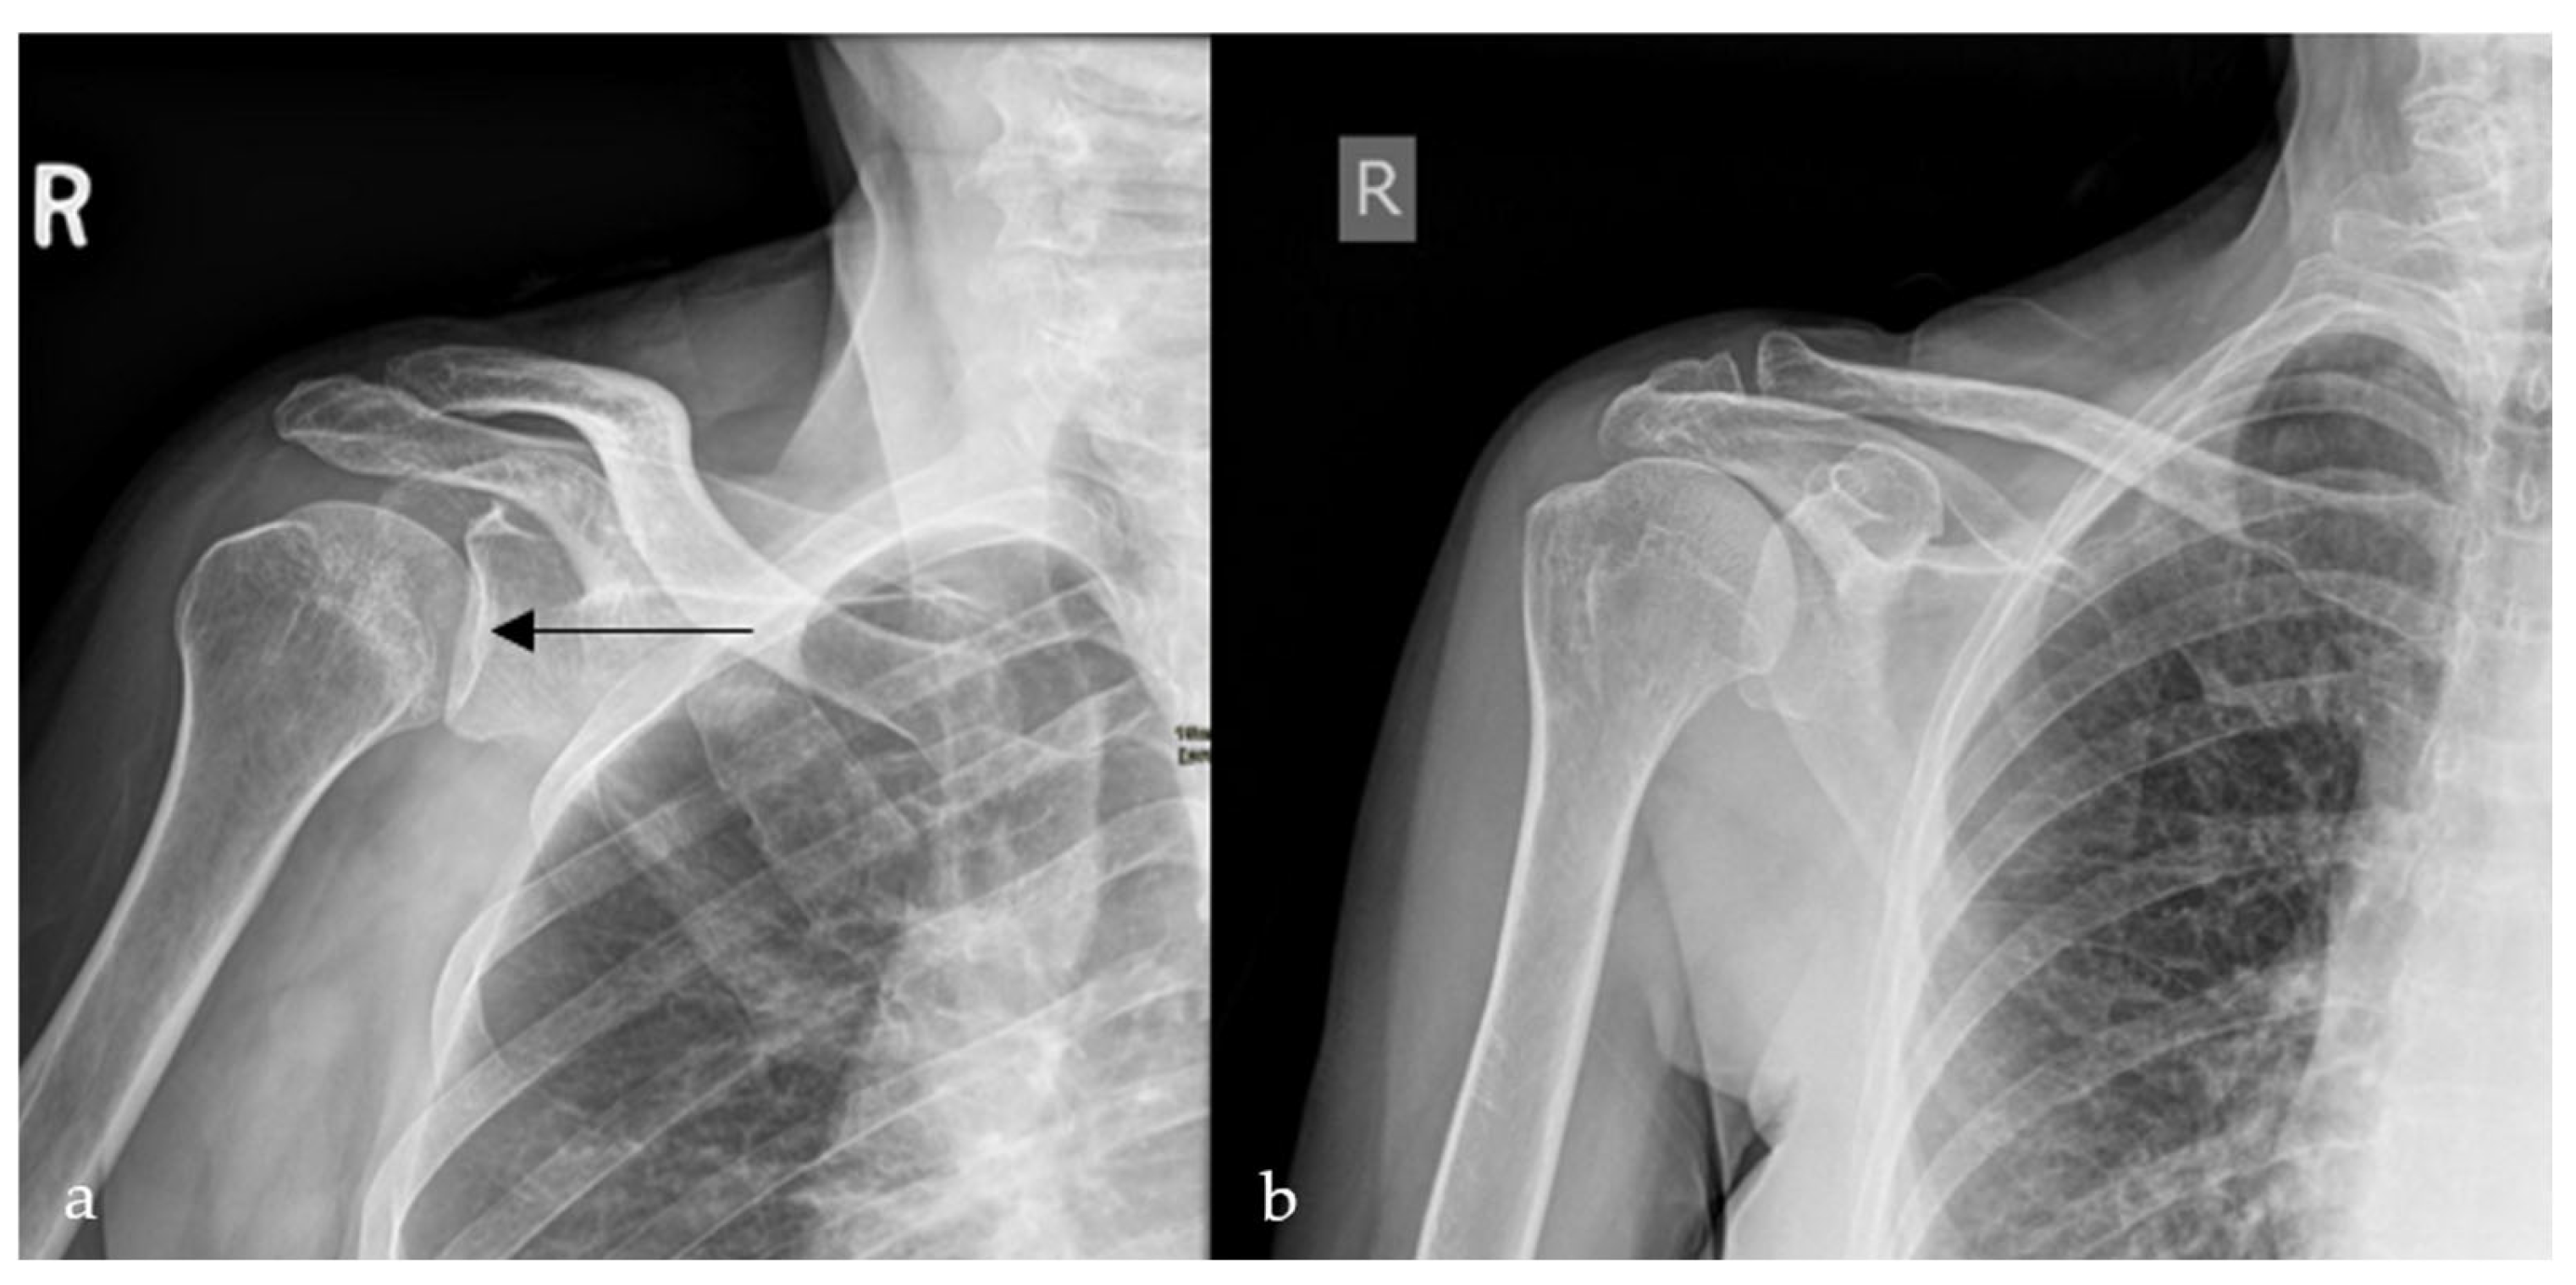

2.4. Loss of Half-Moon Overlap Sign

On a normal anteroposterior shoulder X-ray, there is overlap between the humeral head and the glenoid, giving the appearance of a half-moon (Figure 4b) [23]. In cases of posterior dislocation of the shoulder, the lateral and posterior displacement of the humeral head will result in the loss of this sign. Radiographic signs of posterior shoulder dislocation are more subtle than those of anterior shoulder dislocation, and this may delay diagnosis; hence, the importance of this sign (Figure 4a) [24]. In shoulder trauma with limited external rotation, loss of half-moon overlap on the AP view increases suspicion for posterior dislocation and expedites reduction, preventing missed injuries.

Figure 4.

Plain radiograph of the shoulder showing lateral displacement of the humeral head with respect to the glenoid, losing the half-moon overlap (black arrow) (a), compared to a plain radiograph of a normal shoulder, illustrating the half-moon overlap (b).